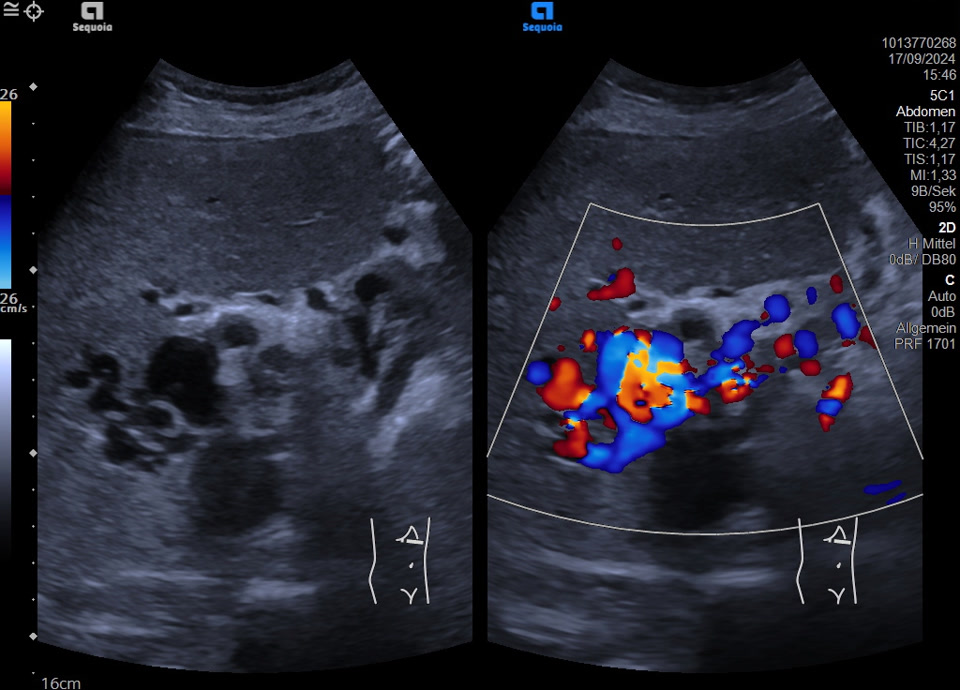

Normvariante: A. hepatica propria dorsal der Pfortader gelegen im proximalen Hilus (meist ist hier die A. hepatica zwischen DHC und Pfortader zu finden)